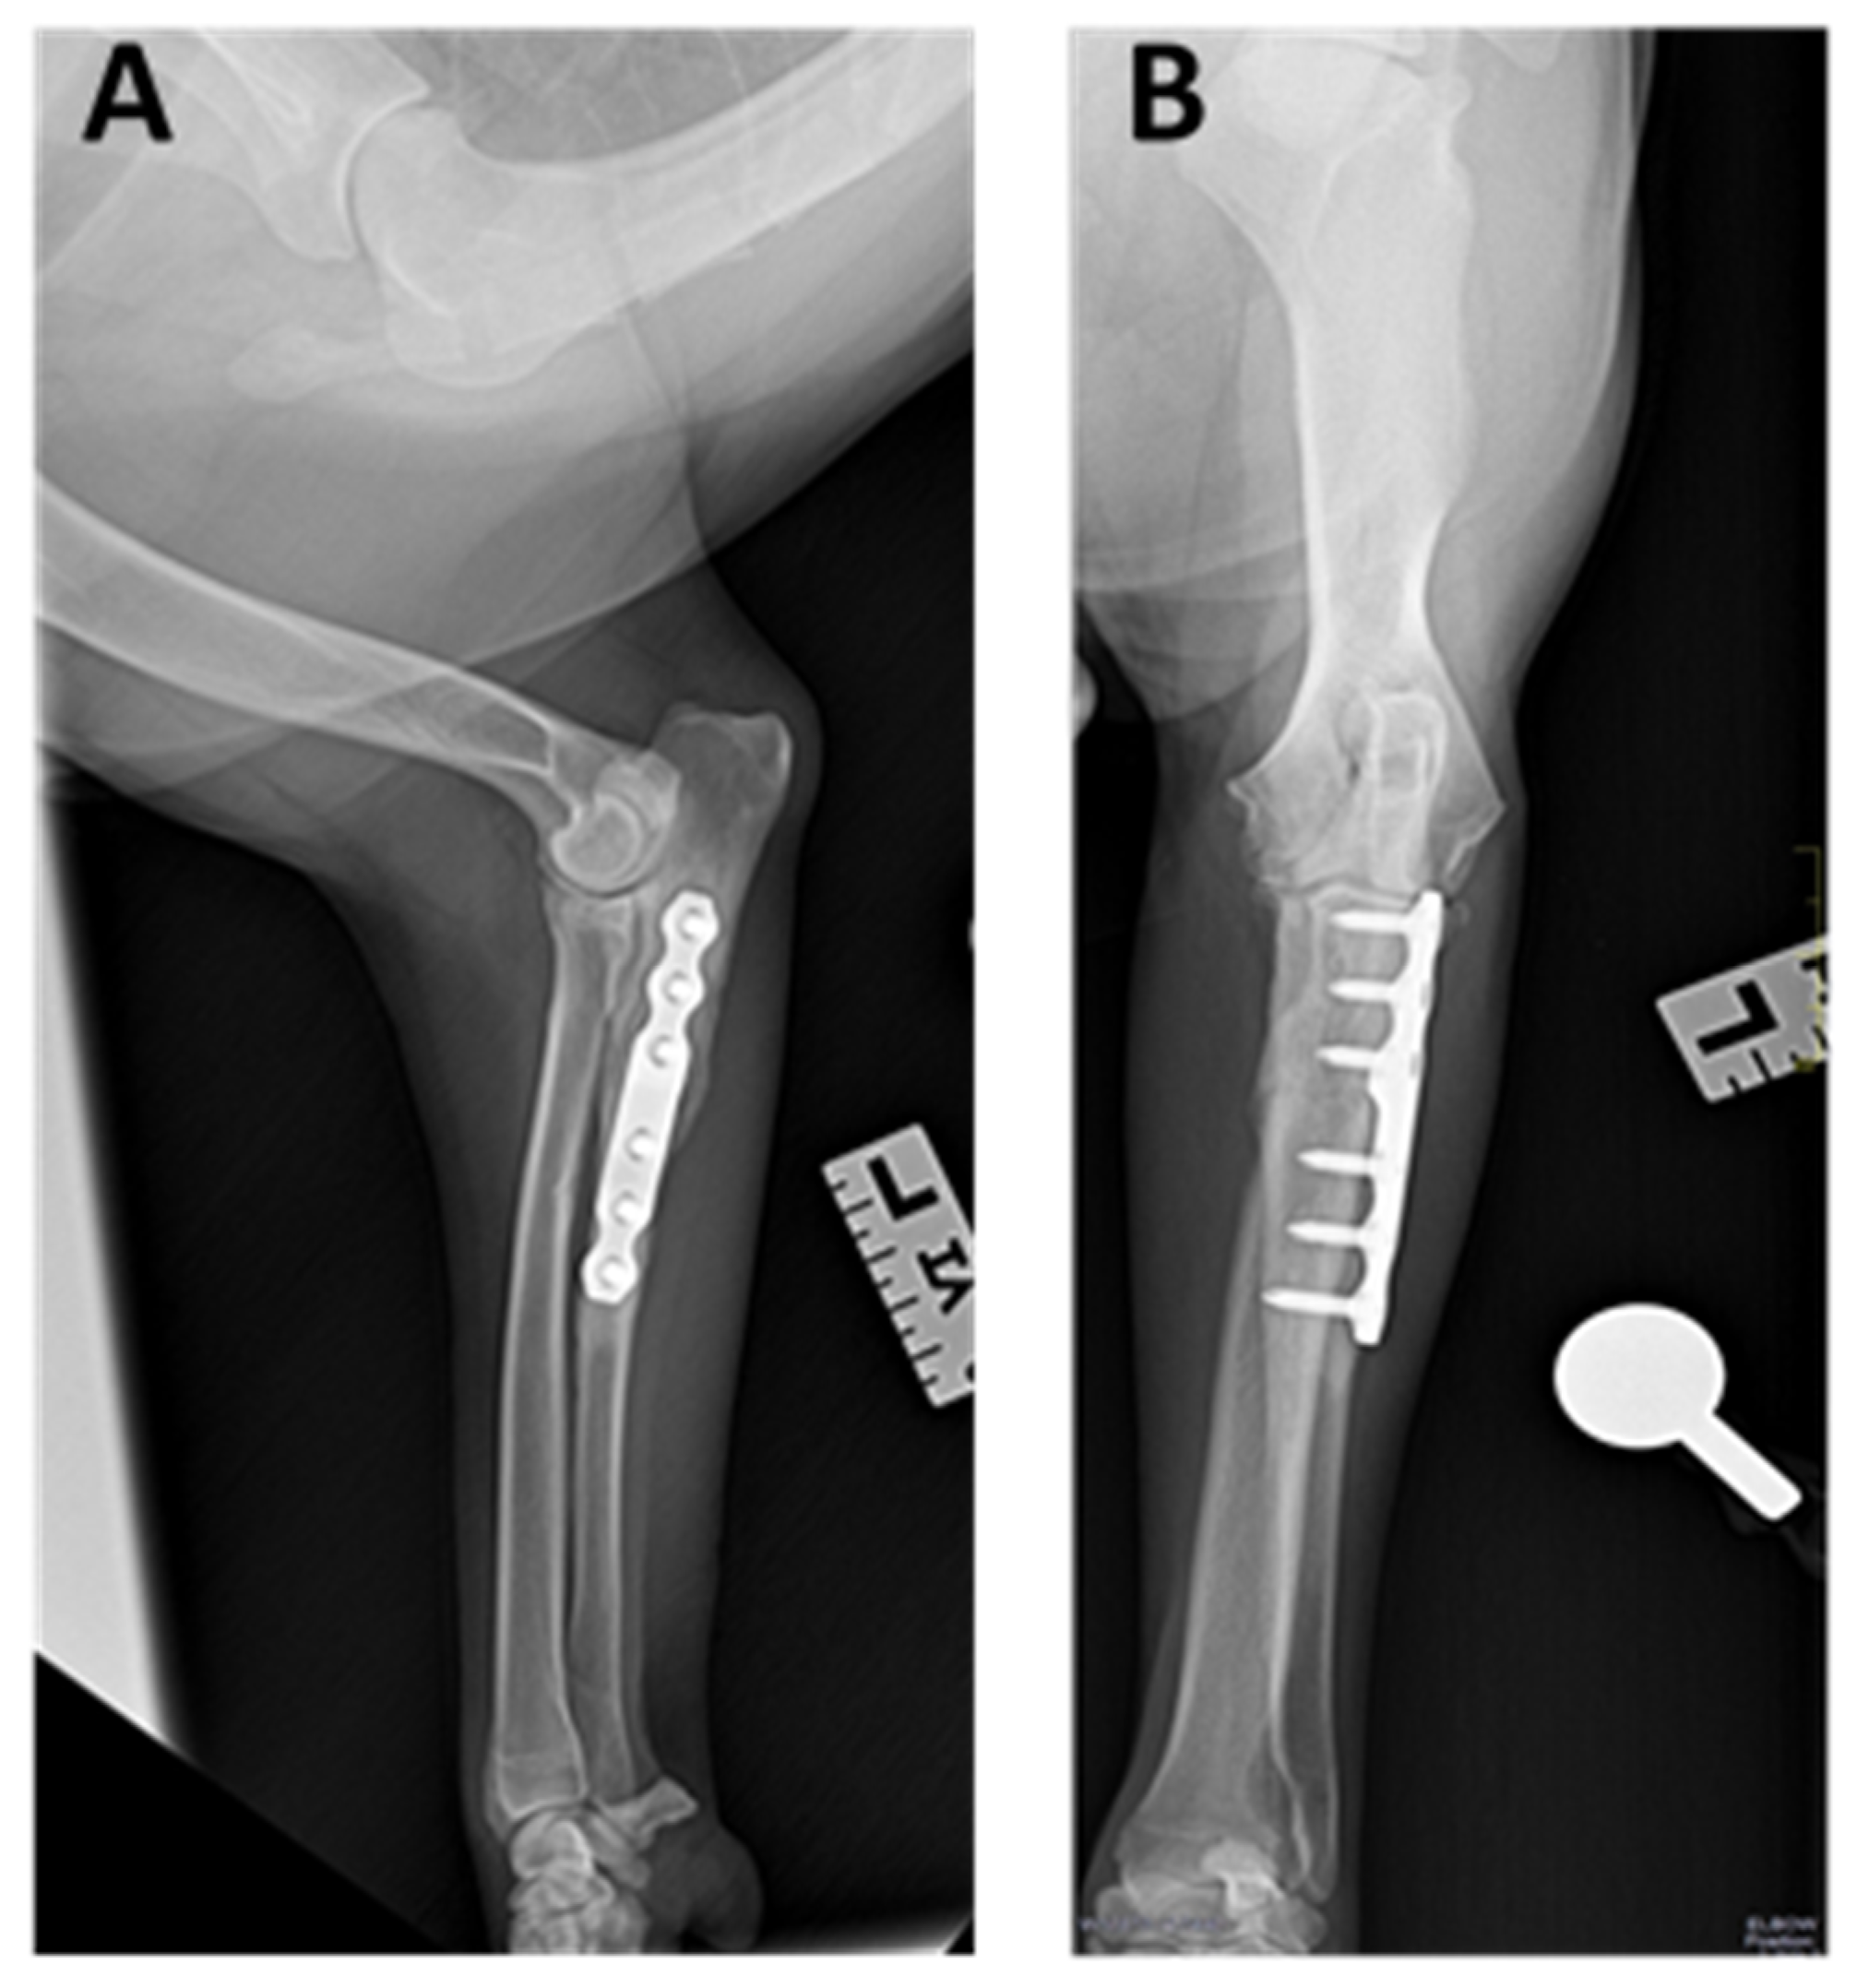

Abstract

2.2. Surgical Procedure

3.3. Radiographic Outcomes

3.4. Minor and Major Complications